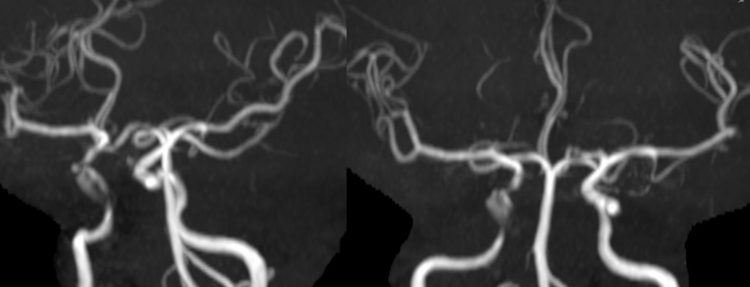

术前MRA提示海绵窦部位血管局限性狭窄扩张,符合动脉瘤的改变。

右侧颈内动脉正侧位DSA造影提示海绵窦段较小动脉瘤,瘤体远近端均存在严重狭窄。

支架释放完后常规正侧位DSA造影显示血管形态良好,动脉瘤充盈明显减少。

双容积重建结果,显示支架和血管壁贴合非常好